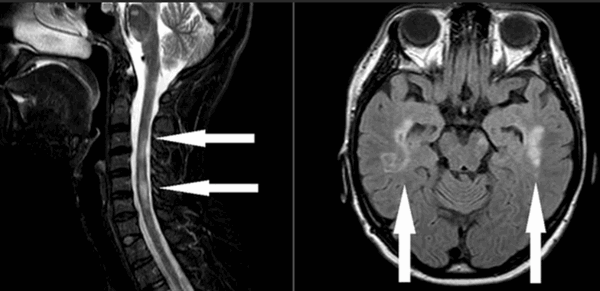

Сканирование головного и МРТ спинного мозга при рассеянном склерозе помогают специалисту увидеть старые и новые очаги, провести ориентировочную дифференциальную диагностику РС с другими заболеваниями. Для определения активности патологического процесса дополнительно применяют контрастное вещество на основе гадолиния: усилитель накапливается в местах обострения воспаления и ярко выделяет их на снимках.

Стрелками на МР-томограммах отмечены участки демиелинизации нервных волокон. Слева - фото спинного мозга (сагиттальная проекция шейного отдела позвоночника), справа - головного (аксиальная плоскость)

Как выглядит рассеянный склероз на МРТ?

Рассеянный склероз на МРТ головного мозга выглядит как пятна округлой формы диаметром до 2 сантиметров, которые по мере развития патологии могут сливаться. Оттенок измененных участков зависит от стадии болезни и бывает светлым, темным или идентичным здоровым тканям (без контраста не выделяется).

Классическим признаком рассеянного склероза на МР-снимках головного мозга являются бляшки линейной формы, располагающиеся перпендикулярно боковым желудочкам. Их называют “пальцы Доусона”.

В спинном мозге очаги демиелинизации выглядят как удлиненные образования, распространяющиеся из центра на периферию с вовлечением в патологический процесс задних рогов.